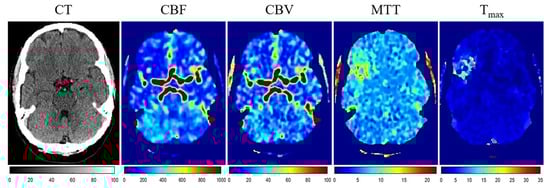

| CT, CBV, Tmax | 0.53 ± 0.22 | 0.56 ± 0.19 |